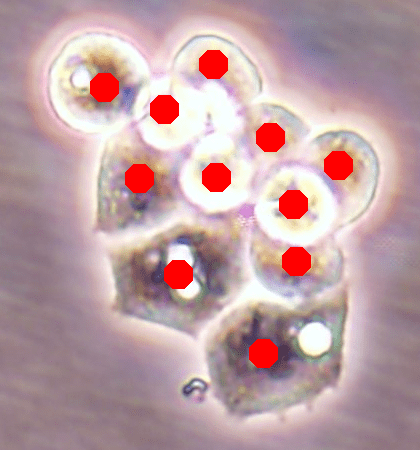

![]() |

| (a) | (b) |

| (c) | (d) |

For an example subimage given in Fig. 2a, these distance definitions are illustrated in Figs. 2b and 2c, respectively. The inner distance definition well indicates the cell centers since it uses the Euclidean distances from pixels to their closest cell centers. However, as it uses the centers as the reference point, the distance decrease from a center to its boundaries is the same for all directions and for all cells. Thus, when it is used alone, this definition imposes a circular and one-sized shape on the cells, as also seen in Fig. 2b. On the contrary, since the normalized outer distance is calculated with a reference to a cell boundary, this decrease may differ from one direction to another as well as from one cell to another, depending on the shape and size of the cell. Thus, it better preserves the morphological characteristics of cells, as seen in Fig. 2c.

The proposed DeepDistance model considers cell detection as a multi-task regression problem that estimates two distance maps from the RGB image, one for formulating the main task of cell detection and the other as an auxiliary task with the motivation of more effectively learning the main task. The FCN architecture given in the previous section is designed to learn these two regression tasks at the same time. This section discusses how this model can be extended to cover more auxiliary tasks, concurrent learning of which may further increase the performance of the main task. For this purpose, this section implements an extended version of the DeepDistance model that comprises an additional task of cell pixel classification. This additional task aims to construct a classification map (as shown in Fig. 2d) from the shared features of the encoder path111To take overlapping cells apart, and hence to obtain an improved map, cell boundaries are widen and subtracted from the classification map. This improved map is also used in the comparison methods to make fair comparisons.. Note that here, instead of defining another regression problem as the additional task, we use a classification problem in order to demonstrate that the model can easily be extended to cover the auxiliary tasks related with regression as well as classification.